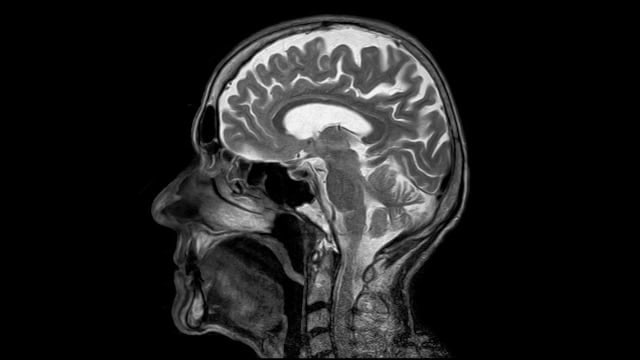

SERANGPOS – Seorang remaja 18 tahun di Faridabad, India, dilarikan ke Instalasi Gawat Darurat (IGD) Rumah sakit ESIC Medical College ketika mengalami kejang-kejang tak terkendali. Saat dokter memeriksa dengan alat magnetic resonance imaging (MRI) ada banyak bintik putih misterius di otaknya.

Saat diperiksa dokter menemukan bintik putih yang ternyata adalah kista dari cacing pita Taenia solium. Seseorang bisa terinfeksi cacing ini ketika mengonsumsi daging yang tidak dimasak dengan matang.

Pada kasus sang remaja dokter menemukan banyak kista cacing mulai dari bagian luar otak besar (serebral korteks) hingga ke dalam otak kecil (serebelum). Dokter bahkan menemukan kista cacing pita di mata kiri dan testis sang remaja.